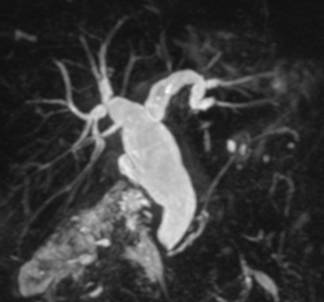

По клинической симптоматике пациенты были разделены на две группы: ,40%) – с синдромом болевой механической желтухи,,60%) – с синдромом безболевой механической желтухи. Причинами обтурационной желтухи у ,91%) пациентов явились: желчнокаменная болезнь, холедохолитиаз (Рис. 1), у,73%) – заболевания (опухолевые и неопухолевые) желчных протоков, прочие болезни панкреатобилиарной зоны, вызывающие внешнюю компрессию желчных протоков (Рис. 2), составили 30,36% (75 больных). (табл. 1).

Рис. 2 МРХПГ. Внутрипеченочная желчная гипертензия, гипертензии в протоке поджелудочной железы за счет образования головки поджелудочной железы.